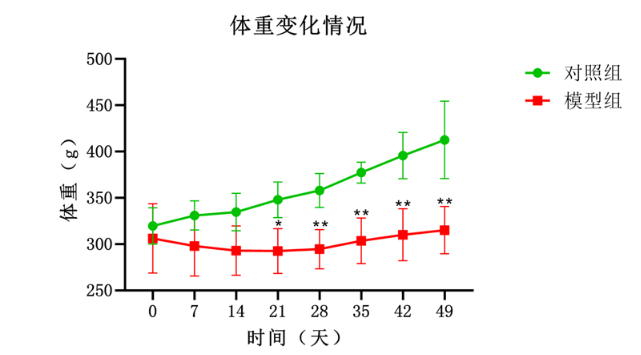

- 模型观察采样:在灌胃过程中和灌胃结束后,密切观察动物的行为学变化、体重变化、毛发色泽改变及精神状态等一般情况。每周称重,记录摄食量及精神状态;造模4周后禁食12 h,麻醉下心脏采血分离血清;取肝、脑组织,部分福尔马林固定(病理切片),部分液氮速冻(分子检测)。

对照组、模型组体重情况

- 模型特点:乙醇灌胃诱导的慢性酒精中毒模型具有诱发因素明确、操作方法简便、实验重复性好等优点。同时,该模型能够较好地模拟人类长期过量饮酒导致的慢性酒精中毒状态,包括行为学改变、生理生化指标异常以及组织病理学改变等。

五、模型总结:乙醇灌胃诱慢性酒精中毒模型通过模拟人类长期饮酒的代谢途径及病理进程,为酒精相关疾病研究提供高度可靠的平台。其核心优势在于:可控性强:梯度浓度设计避免急性毒性,死亡率<10%;病理全面:同步复制肝、脑、肌等多系统损伤;标准化操作:勋博生物建立标准化灌胃流程及质控体系,确保批次间一致性,可用于研究慢性酒精中毒的相关问题。在实验过程中需注意细节控制,以确保实验结果的准确性和可靠性。